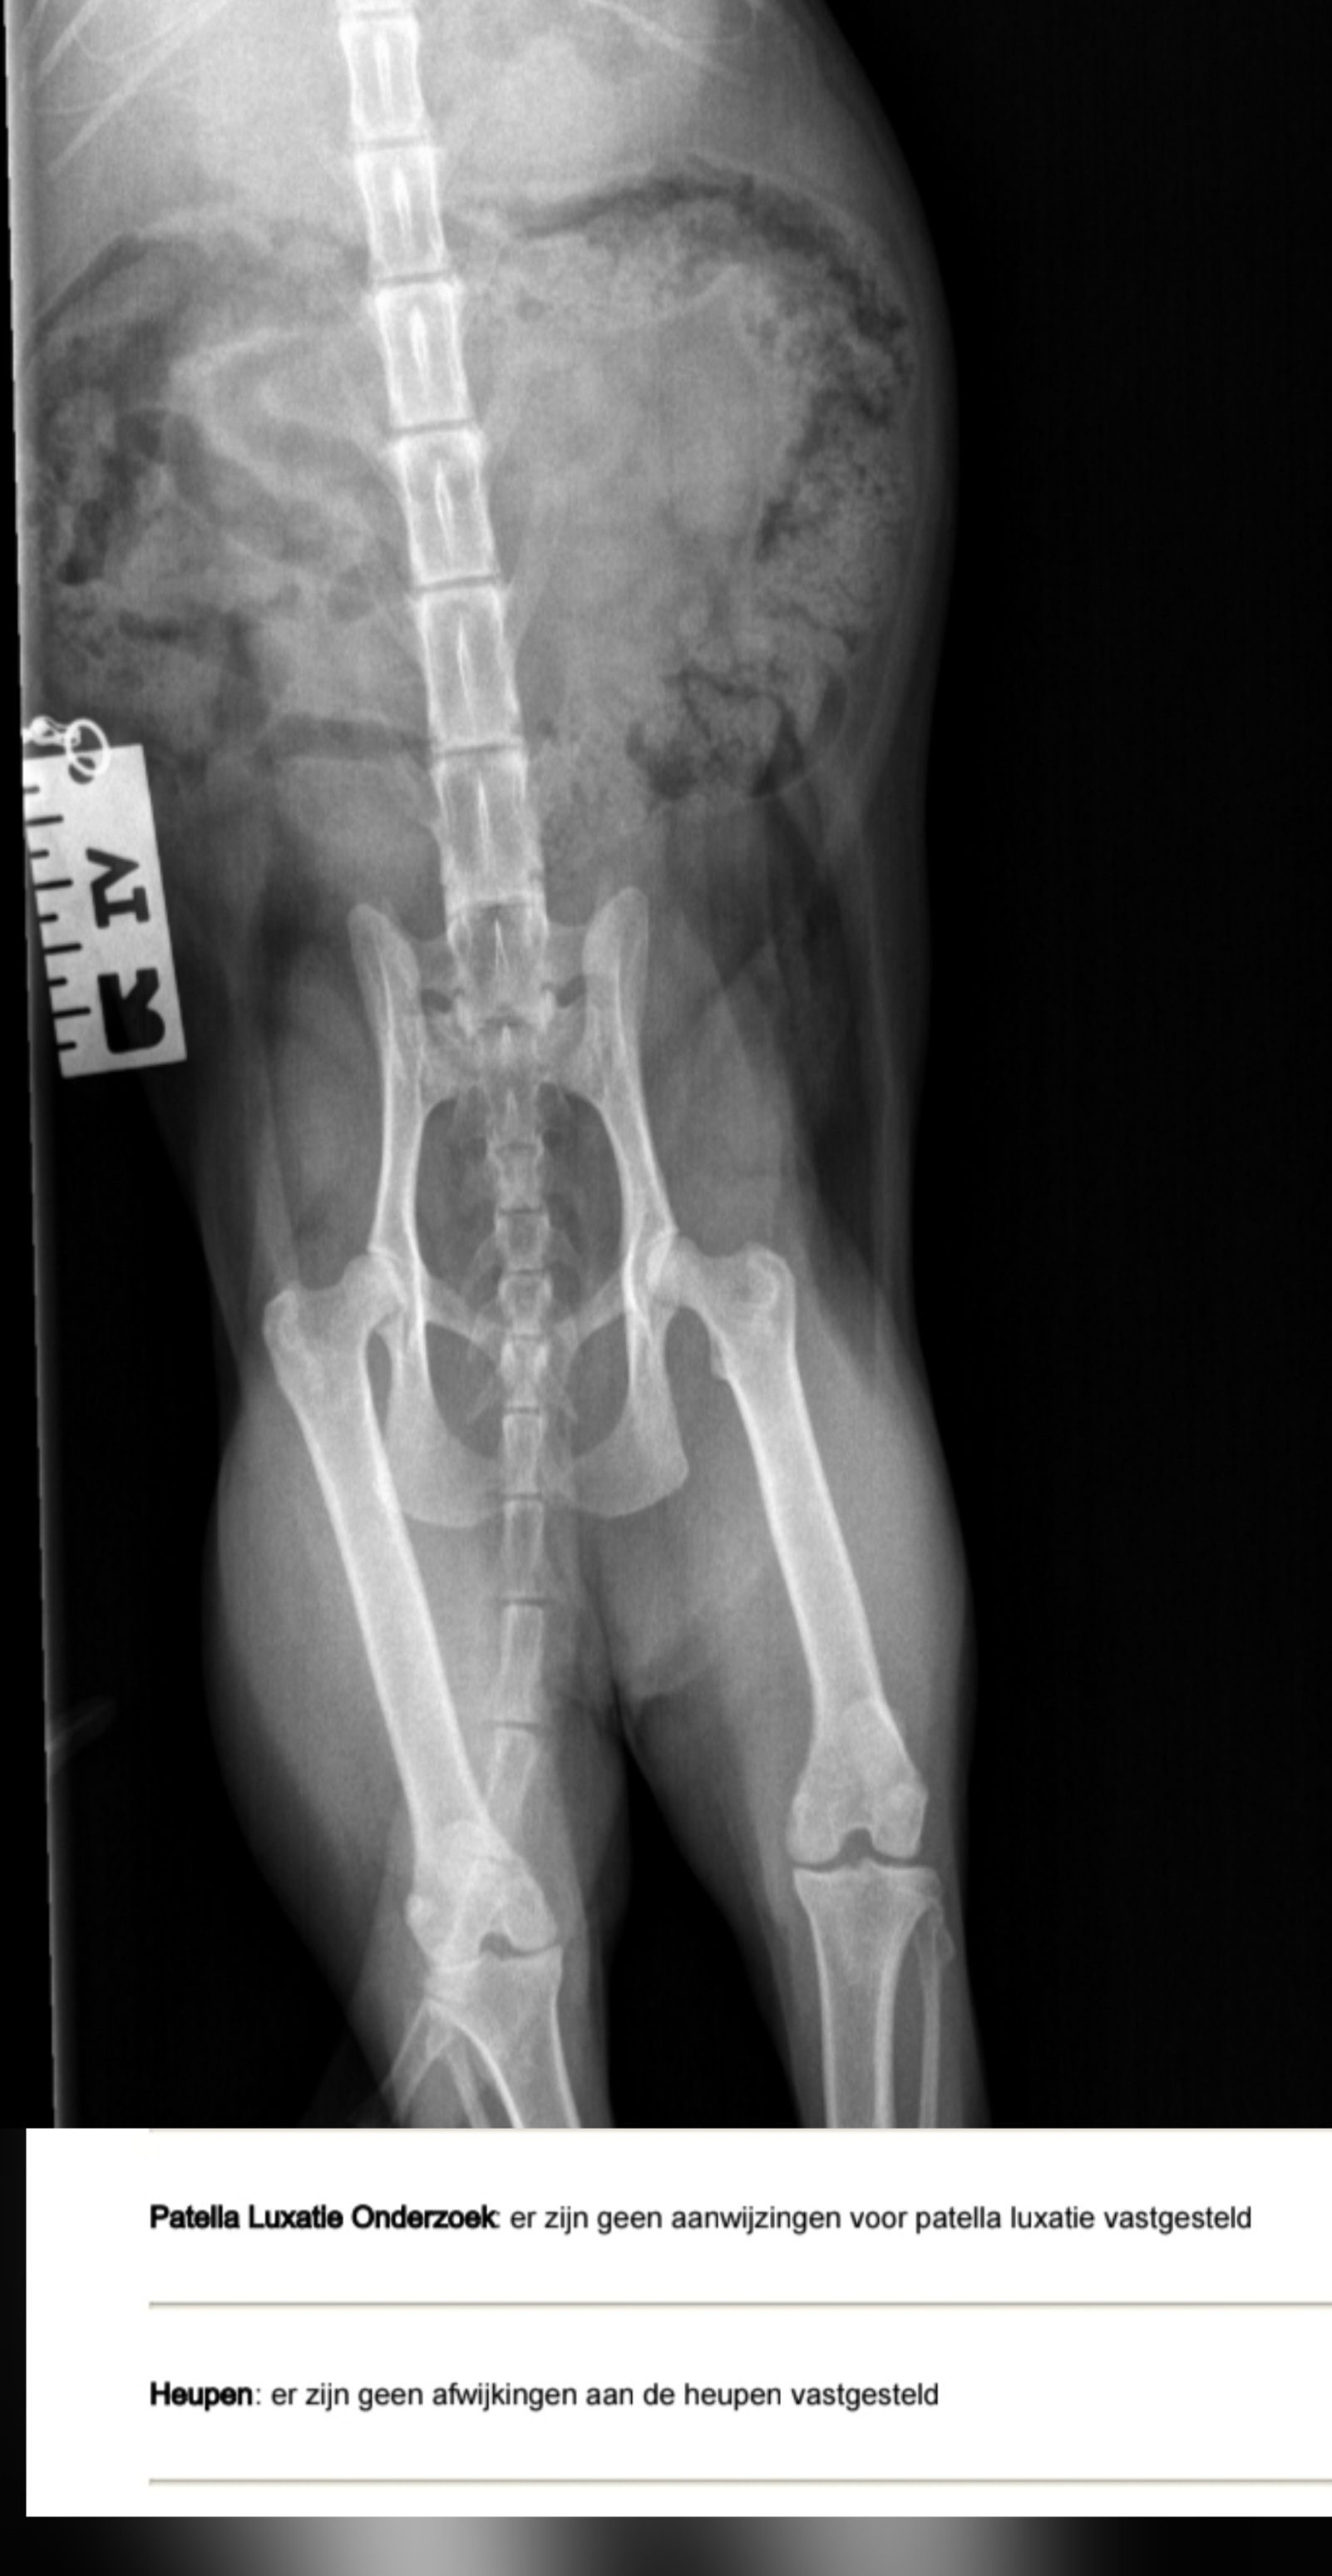

Heupen Knieen 👌

Afbeelding – 504,2 KB

53 downloads

Download